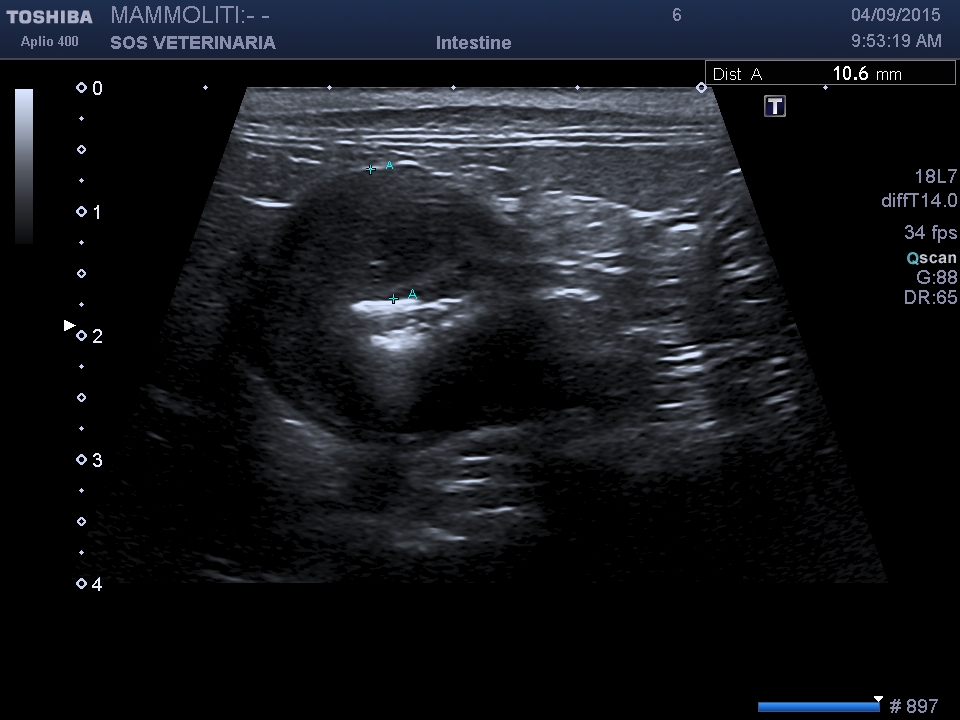

linfoma gastrico

gatta, comune europea,7 anni , emesi ricorrente da diversi mesi ,analisi del sangue nulla di significativo ,alla palpazione profonda dell’addome si avvisava sensazione di duro a livello gastrico ,l’esamo ecografico normalmente poco scarsamente sensibile e specifico per le patologie gastriche ,in questo caso, molto avanzato, ha evidenziato l’ispessimento della parete,  eseguita il giorno dopo la gastroscopia  ha confermato purtroppo la diagnosi ,

scansione trasversale